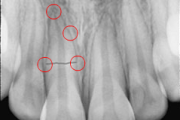

Alveolaarjätke murd